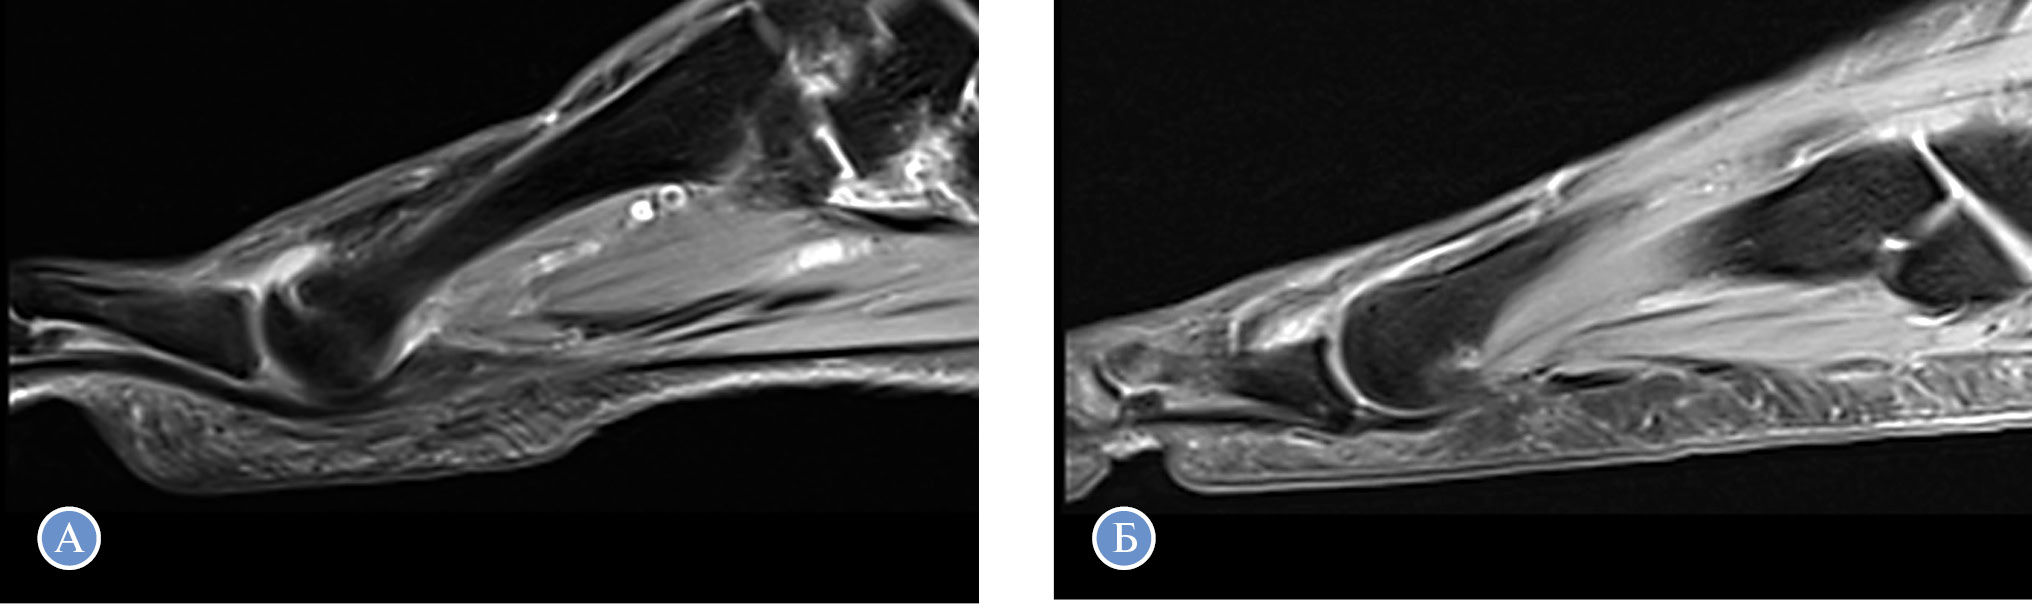

Лучевые методы диагностики включают рентгенографию стоп под нагрузкой в двух проекциях, компьютерную томографию стоп под нагрузкой. Для диагностики разрыва подошвенной связки можно также использовать магнитно-резонансную томографию (рис. 1).

Рис. 1. Пациент В., 63 года. Визуализация подошвенной связки 2-го и 3-го плюснефаланговых суставов правой стопы с помощью магнитно-резонансной томографии

Примечание. А — разрыв подошвенной связки 2-го плюснефалангового сустава по данным магнитно-резонансной томографии; B — интактная подошвенная связка и отсутствие разгибательной деформации на уровне 3-го плюснефалангового сустава.